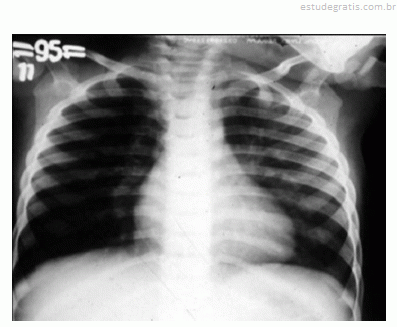

Um lactente de quatro meses de idade cronológica, nascido prematuro de vinte e nove semanas gestacionais, apresentou, durante o inverno, febre, tosse e dificuldade respiratória nos últimos três dias antes de ser levado por sua mãe à emergência pediátrica. A mãe relatou que a criança nunca havia apresentado um episódio semelhante a esse. O calendário vacinal mostrou que a criança recebeu duas doses da vacina antipneumocócica decavalente, porém não recebeu palivizumabe. O exame físico da criança mostrou desidratação, taquipnéia, retração intercostal e sibilos inspiratórios e expiratórios. O resultado do hemograma solicitado pelo médico revelou hematócrito de 40%, concentração de hemoglobina de 13 g/dL, 9.000 leucócitos/mm3, 55% de linfócitos, 34% de neutrófilos, 2% de eosinófilos, 1% de basófilos, 8% de monócitos, 340.000 plaquetas/mm3. O médico solicitou radiografia de tórax da criança, cuja imagem é apresentada na figura.

Nesse caso, a pneumonia bacteriana não configura um diagnóstico diferencial, pois se trata do primeiro episódio de dificuldade respiratória com broncoespasmo. Além disso, a radiografia do tórax não mostra áreas de atelectasia ou condensação.Comentários